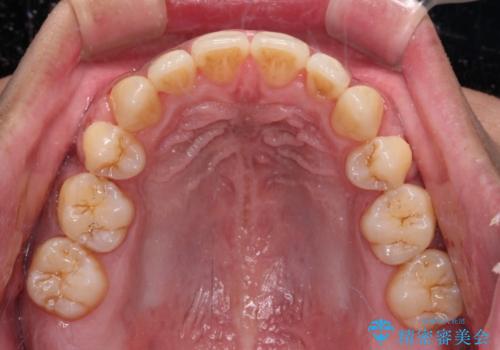

舌の突出癖を改善するためのトレーニングを指導していましたが、なかなか改善することができず、ワイヤー装置を外してからも上下前歯に隙間ができやすい状況でした。